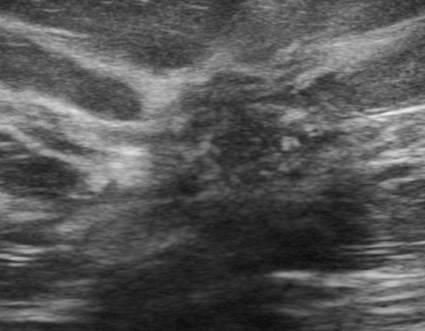

What is a Complex Cysts?

benign breast condition

contain some low level internal echotexture or intra-cystic debris.

Risk of malignancy among complicated breast cysts is thought to be 0.3-2%

What is the Sonographic Appearance of Complex Cysts?

Low to medium echogenicity

Irregular walls

hetertogenous

fluid filled levels

septations

wall thickening

debris

varying degrees of shadowing